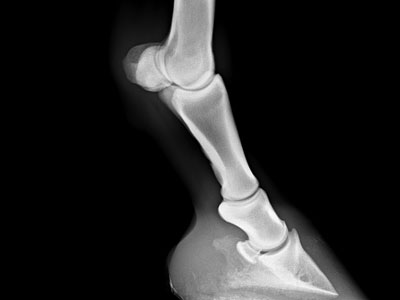

Orthopädie

Lahmheitsuntersuchung inklusive Leitungs- und Gelenksanästhesie und Behandlung, Röntgen, orthopädischer Ultraschall

mobiles digitales Röntgen digitales Röntgen am Pferd